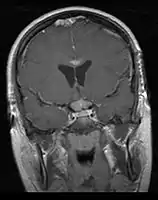

- Mainly located in midline structures, suprasellar region or pineal gland, also basal ganglia and hypothalamus

Location

- Pineal Gland Germinoma

- Suprasellar Germinoma